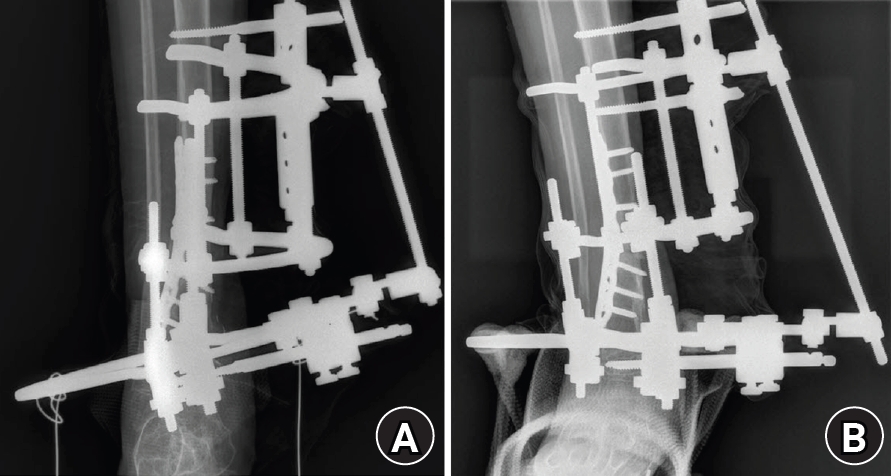

An 8-year-old girl presented after a traffic accident with a severe crush and degloving injury of the medial right ankle and foot, a distal tibiofibular fracture, and medial midfoot bone defects. After staged irrigation and debridement with temporary external fixation, definitive reconstruction was performed on August 6, 2016. The medial malleolar defect (2.5×2.0 cm) was reconstructed using a contoured autologous iliac crest bone graft secured with internal fixation, and medial stability was augmented using harvested gluteal fascia as a deltoid ligament substitute fixed with suture anchors. A bone-cement spacer was placed adjacent to the injured physis to mitigate physeal bridging, and the extensive soft-tissue defect was covered with a free anterolateral thigh flap and skin graft. During follow-up, progressive varus deformity and contracture were managed with corrective osteotomy and plating, Achilles tendon lengthening, Z-plasty, and Ilizarov fixation. At the final follow-up (March 6, 2025), the limb-length discrepancy was 5 mm, active ankle dorsiflexion was 0° (passive dorsiflexion 5°), and the patient was pain-free with full participation in daily activities, including hiking and dancing. This case emphasizes the value of an integrated staged strategy that combines bony reconstruction, medial stabilization, physeal management, and durable soft-tissue coverage during skeletal growth.